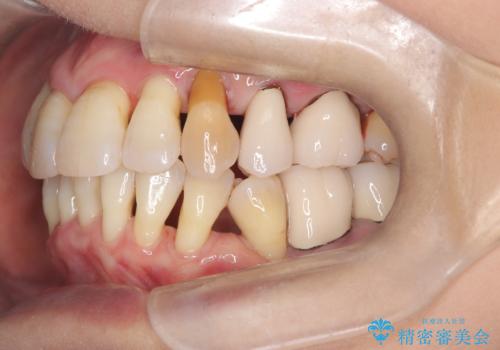

- 歯周病で歯茎が下がり根っこの部分が見えている状態で3か月のメンテナンスをコンスタントに通われている方です。

ブラッシングは歯間ブラシや部分歯ブラシなどの補助道具も使用し時間をかけて丁寧に磨いていらっしゃるのですが、ブラッシング圧に気を付けながらの為バイオフィルムが根っこの部分に残っているのです。

いつも時間をかけて丁寧に磨いていらっしゃるようですが染め出しをしてみると歯茎が下がっている部位はバイオフィルムの付着が見られました。

患者さまに説明してエアーフロー施術しこれから定期的に施術希望になりました。